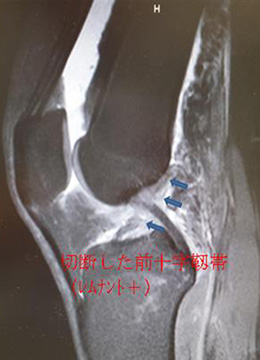

自分の組織を用いて再建する(自家腱移植)のがベストな方法とされています。当院で行っている膝屈筋腱(ハムストリングス)を用いた関節鏡視下膝前十字靱帯再建術は、切開は最小限で大きな合併症がなく、術後の成績も安定しているため、有効な治療方法として確立されています。 手術は膝関節を構成する大腿骨と脛骨の最適部位に関節鏡を用いて細いトンネルを作製し、そこに採取加工した腱を貫いて上端と下端を金具で固定することで膝の安定性を得ることを目的とし、全身麻酔+硬膜外持続麻酔下で行います。尚、本院では遺残靱帯(レムナント)が残存している患者様に対しては再生医療の観点※からレムナントを切除せずレムナントを利用し一重束前十字靱帯再建術(レムナント温存法)を、また女性で膝が柔らかい患者様(反張膝の患者様)などには二重束前十字靱帯再建術を、また二度目の受傷の患者様などには膝蓋腱を用いて一重束前十字靱帯再建術(BTB法)をおこなっています。また、縫合可能な半月板損傷がある患者様に対しては全例半月板縫合を行います。(Biomet MaxFire™ を利用し、関節内だけの操作で縫合します。)手術時間はレムナント温存法で行った時は約1時間から1時間半です。